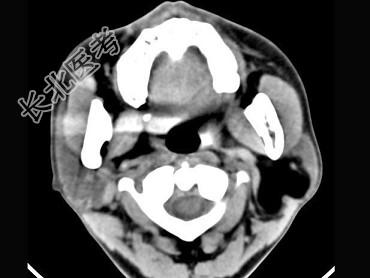

- 多项选择题男,38岁, 左侧腮腺渐进性肿大1年,无压痛, CT扫描如图所示,正确的描述或诊断是 ( )

A、左侧腮腺区见低密度肿块,CT值约为-200Hu

B、肿块边缘清楚,未见邻近结构受侵

C、囊肿

D、脂肪瘤